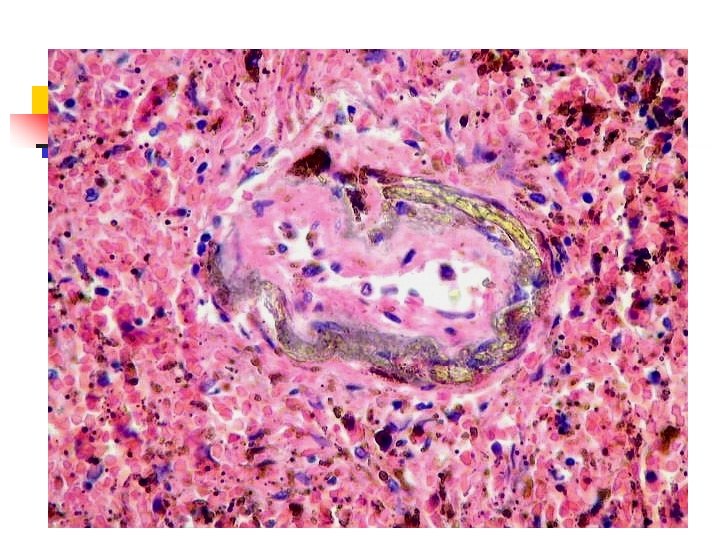

Mieloma múltiple n n Nefrosis del mieloma ( histología ) : Infiltrados intersticiales de CP Cilindros proteínicos: *en TCD, colectores. * Proteínas de Bence Jones, Igs completas *Propiedad tintorial del amiloide. *Rodeados de células gigantes multinucleada Necrosis o atrofia de células tubulares.

Mieloma múltiple n n n n Nefrosis del mieloma ( histología ): Calcificación metastásica Amiloidosis Pielonefritis. ASPECTOS CLINICOS: Incidencia máxima: 50 - 60 años. Sexo: sin predilección.